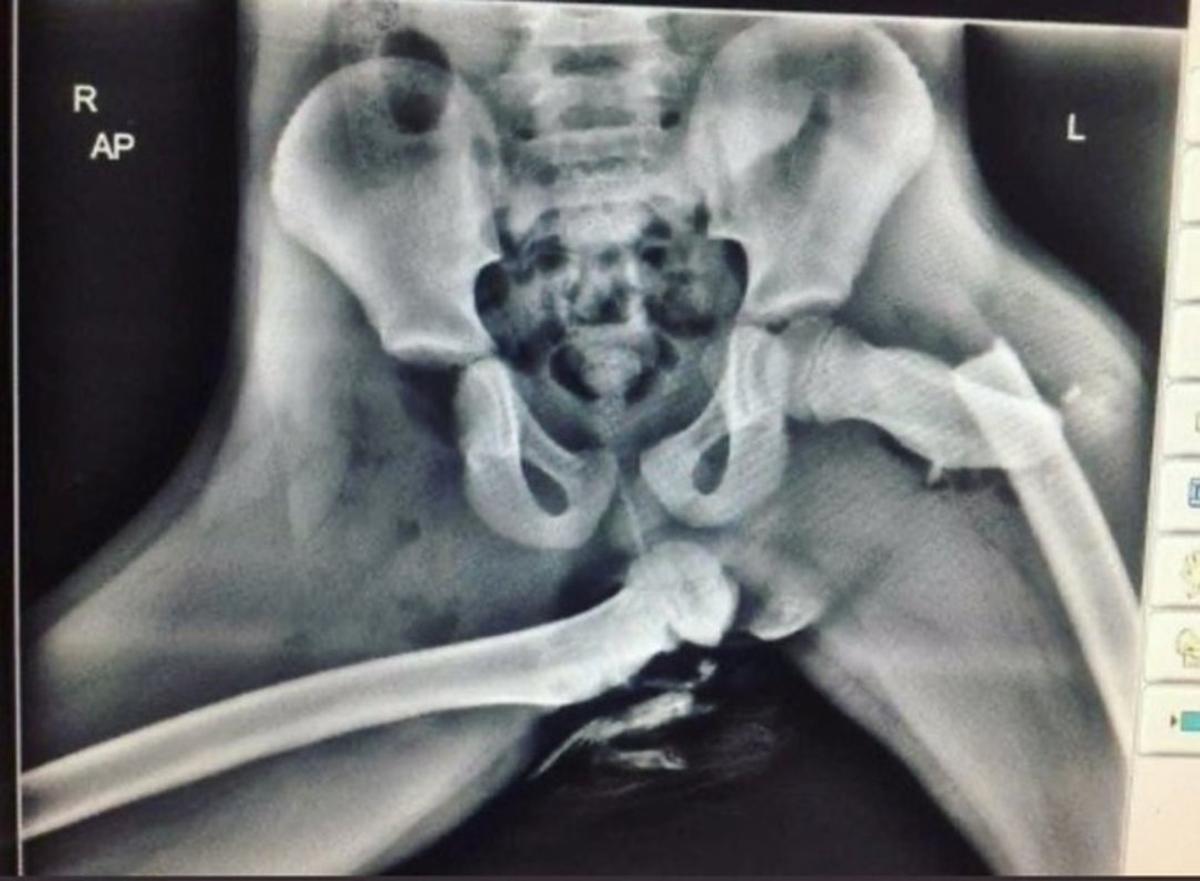

Dashboard fracture. Frontal view of the pelvis shows a posterior Feet On The Dashboard Xray  Seems like a harmless way to relax, right? Georgia mom audra tatum is using her story to warn others not to put their feet up on the dashboard. A passenger in the front seat of a car with their feet resting on the dashboard. Unfortunately not, especially if your car has airbags. The injuries in a crash could be severe,. Feet On The Dashboard Xray.

Horrific Xray image shows why you shouldn't put your feet on your car Feet On The Dashboard Xray  Seems like a harmless way to relax, right? Unfortunately not, especially if your car has airbags. You surely know that riding with feet up on the dashboard is unsafe. Georgia mom audra tatum is using her story to warn others not to put their feet up on the dashboard. The injuries in a crash could be severe, and even a. Feet On The Dashboard Xray.

Horrifying Xray shows why you should not put your feet on car Feet On The Dashboard Xray  The injuries in a crash could be severe, and even a minor. Seems like a harmless way to relax, right? You surely know that riding with feet up on the dashboard is unsafe. A passenger in the front seat of a car with their feet resting on the dashboard. Unfortunately not, especially if your car has airbags. Georgia mom audra. Feet On The Dashboard Xray.

Welsh police officer shares XRay that shows why you should never put Feet On The Dashboard Xray  Seems like a harmless way to relax, right? You surely know that riding with feet up on the dashboard is unsafe. The injuries in a crash could be severe, and even a minor. Unfortunately not, especially if your car has airbags. Georgia mom audra tatum is using her story to warn others not to put their feet up on the. Feet On The Dashboard Xray.

This horrific Xray shows why you shouldn't put your feet upon your car Feet On The Dashboard Xray  The injuries in a crash could be severe, and even a minor. Seems like a harmless way to relax, right? Unfortunately not, especially if your car has airbags. You surely know that riding with feet up on the dashboard is unsafe. A passenger in the front seat of a car with their feet resting on the dashboard. Georgia mom audra. Feet On The Dashboard Xray.

Shocking Xray shows why you should never put your feet on the Feet On The Dashboard Xray  You surely know that riding with feet up on the dashboard is unsafe. The injuries in a crash could be severe, and even a minor. Unfortunately not, especially if your car has airbags. Georgia mom audra tatum is using her story to warn others not to put their feet up on the dashboard. Seems like a harmless way to relax,. Feet On The Dashboard Xray.

Xray reveals woman’s crushed hips after resting feet on car dashboard Feet On The Dashboard Xray  Seems like a harmless way to relax, right? The injuries in a crash could be severe, and even a minor. Unfortunately not, especially if your car has airbags. You surely know that riding with feet up on the dashboard is unsafe. A passenger in the front seat of a car with their feet resting on the dashboard. Georgia mom audra. Feet On The Dashboard Xray.

This xray shows why you should never rest your feet on the dashboard Feet On The Dashboard Xray  A passenger in the front seat of a car with their feet resting on the dashboard. The injuries in a crash could be severe, and even a minor. Georgia mom audra tatum is using her story to warn others not to put their feet up on the dashboard. Seems like a harmless way to relax, right? You surely know that. Feet On The Dashboard Xray.